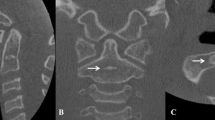

From 709 hand wrist radiographs and CBCT images, 447 samples were randomly selected (called as G1) to build a logistic regression model. The reliability and reproducibility were assessed by the intraclass correlation coefficient (ICC) and weighted Cohen’s kappa, followed by Spearman’s rank correlation coefficient to identify the parameters significantly associated with the SMI. Two hundred and sixty-two other subjects (named G2) were recruited for external examination of the models by direct visual comparison and the receiver operating characteristic (ROC) curve. In cases of confusion and mispredictions, the model was modified to improve the consistency.

Byun BR, Il KY, Yamaguchi T, Maki K, Ko CC, Hwang DS, Park SB, Son WS (2015) Quantitative skeletal maturation estimation using cone-beam computed tomography-generated cervical vertebral images: a pilot study in 5- to 18-year-old Japanese children. Clin Oral Investig 19:2133–2140. https://doi.org/10.1007/s00784-015-1415-6

Byun B-R, Kim Y-I, Yamaguchi T, Maki K, Son W-S (2015) Quantitative assessment of cervical vertebral maturation using cone beam computed tomography in Korean girls. Comput Math Methods Med 2015:405912. https://doi.org/10.1155/2015/405912

All the authors certify that human research participants provided informed consent for publication of their data and radiographic images in Figs. 2 and 3.